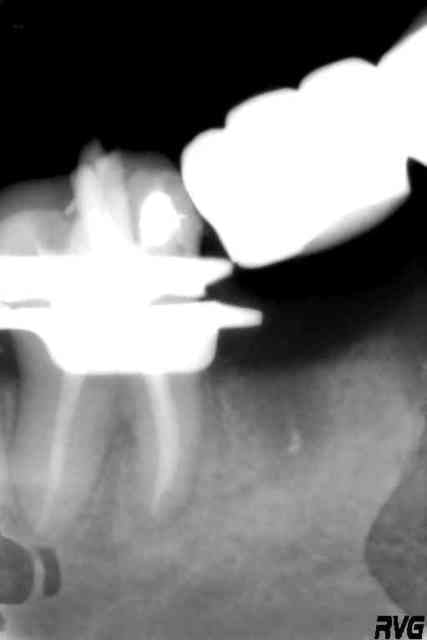

Quand on vient y chercher des idées de plan de traitement

Occlusion ymmem9 - Eugenol